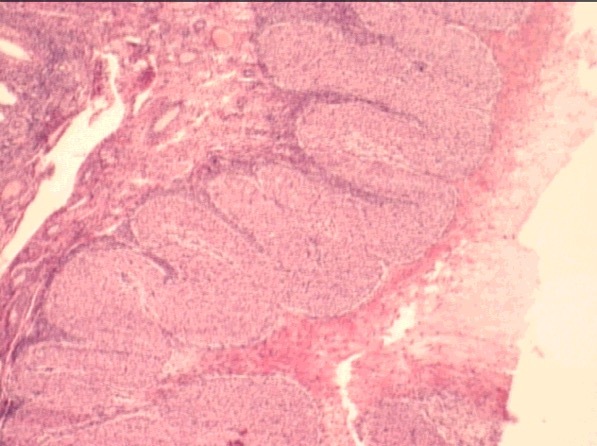

testes

lobules divided by septa

tunica albuginea

seminiferous tubules